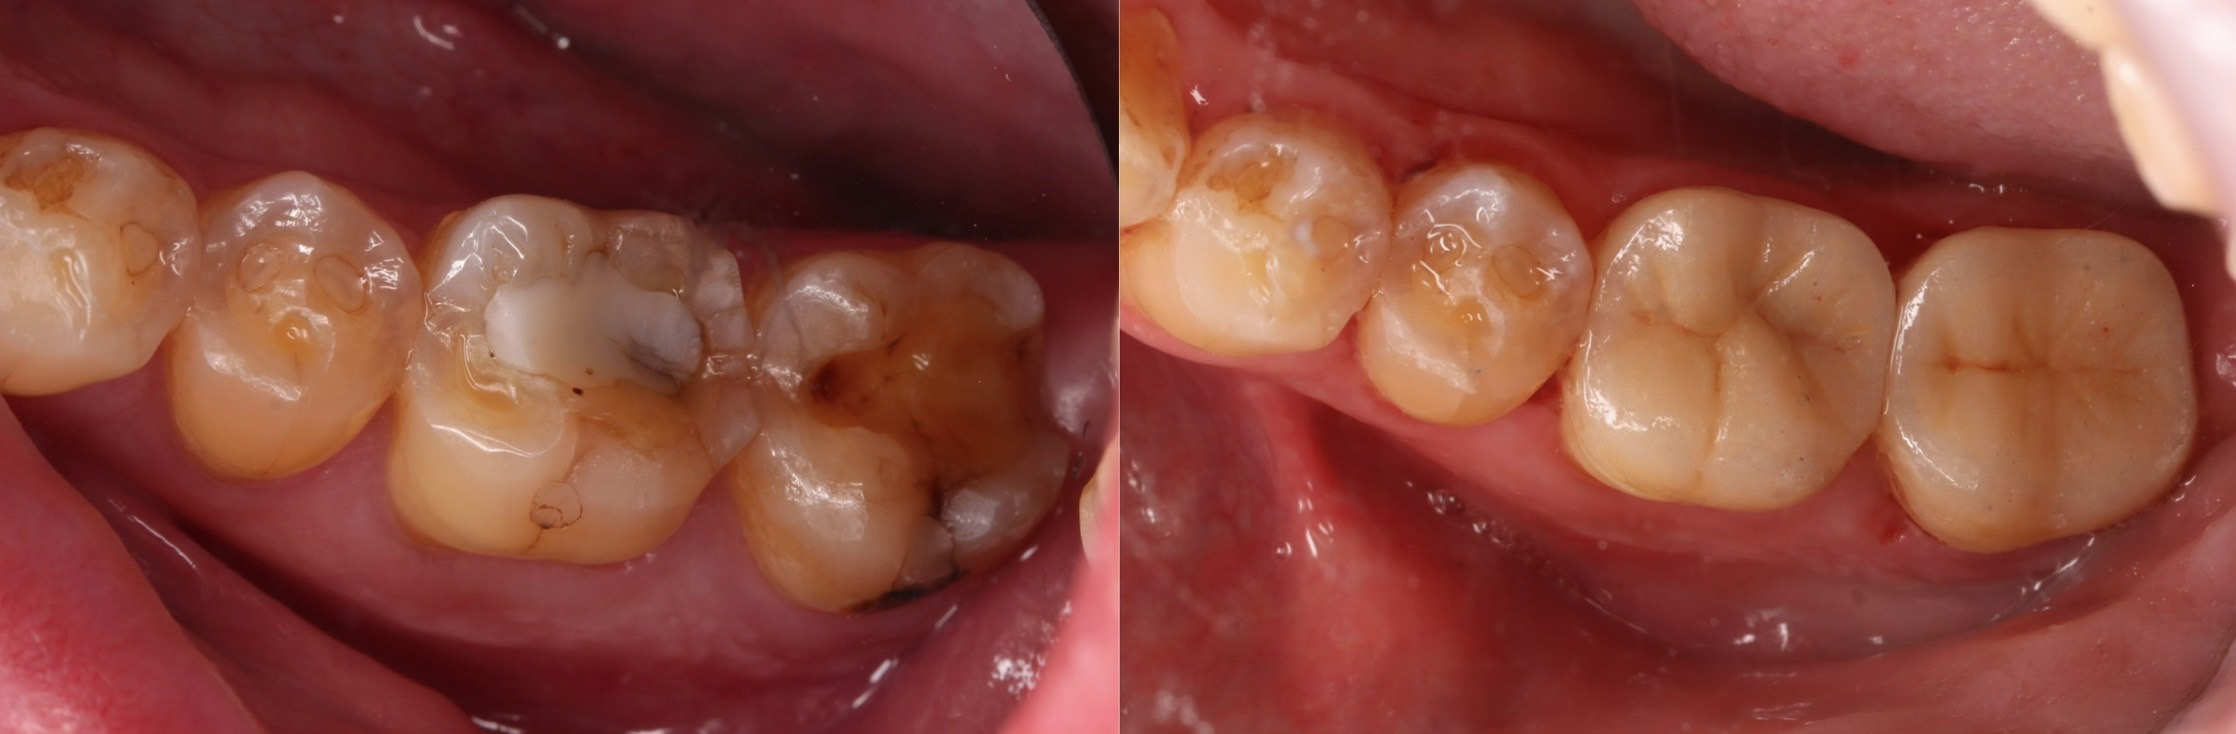

固定式假牙種類2:3D齒雕(嵌體)

利用3D掃描計算缺牙的情形後,牙技師會利用電腦程式製作擬真牙冠,最後黏合在真牙上,是在齒質缺損條件較好的情況下,有機會以更保守的方式保留牙齒齒質的做法。